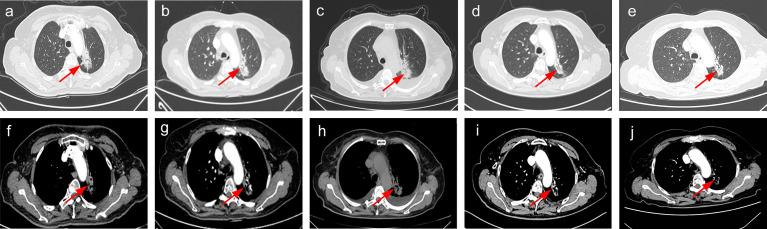

Osimertinib, a third-generation epidermal growth factor receptor tyrosine kinase inhibitor (EGFR-TKI) first-line therapy, has shown good clinical outcomes in non-small cell lung cancer (NSCLC), but some serious adverse events such as cardiotoxicity have also been reported. Here, we present the first NSCLC case with osimertinib-induced cardiac failure. The case is successfully being treated by switching to another third-generation TKI, aumolertinib. A 62-year-old non-smoking woman was initially diagnosed with stage cT2aN2M1c IVB NSCLC with synchronous brain and bone metastasis in April 2020. Further genetic screening of the patient identified Leu858Arg (L858R) mutation in EGFR; thus, the patient was administered third-generation TKI osimertinib (80 mg/day) for 6 months. This treatment with osimertinib led to serious cardiac failure but no significant reduction in NSCLC tumor size. To cope with these conditions, another third-generation TKI, aumolertinib (110 mg/day), along with a supplement treatment plan was prescribed to the patient. Interestingly, this new treatment plan of aumolertinib significantly inhibited tumor growth in 8 months. Therefore, we conclude that the administration of second-line aumolertinib 110 mg/day has fewer adverse reactions and high efficacy against NSCLC as compared to osimertinib therapy.

奥希替尼,一种第三代表皮生长因子受体酪氨酸激酶抑制剂(EGFR-TKI)的一线治疗药物,在非小细胞肺癌(NSCLC)中显示出良好的临床疗效,但也有报道称其存在严重的不良反应,如心脏毒性。在这里,我们报告了首例奥希替尼引起的心衰的 NSCLC 病例。该病例通过改用另一种第三代 TKI,阿美替尼,成功得到治疗。一名 62 岁的不吸烟女性于 2020 年 4 月被最初诊断为 cT2aN2M1c IVB 期 NSCLC,同时伴有脑和骨转移。进一步对患者的基因进行筛选发现存在 EGFR 的 Leu858Arg(L858R)突变;因此,患者接受第三代 TKI 奥希替尼(80 mg/天)治疗 6 个月。奥希替尼治疗导致严重的心衰,但 NSCLC 肿瘤大小无明显缩小。为了应对这些情况,为患者开具了另一种第三代 TKI 阿美替尼(110 mg/天)和补充治疗方案。有趣的是,阿美替尼新的治疗方案在 8 个月内显著抑制了肿瘤生长。因此,我们得出结论,与奥希替尼治疗相比,二线阿美替尼 110 mg/天的给药具有更少的不良反应和更高的 NSCLC 疗效。